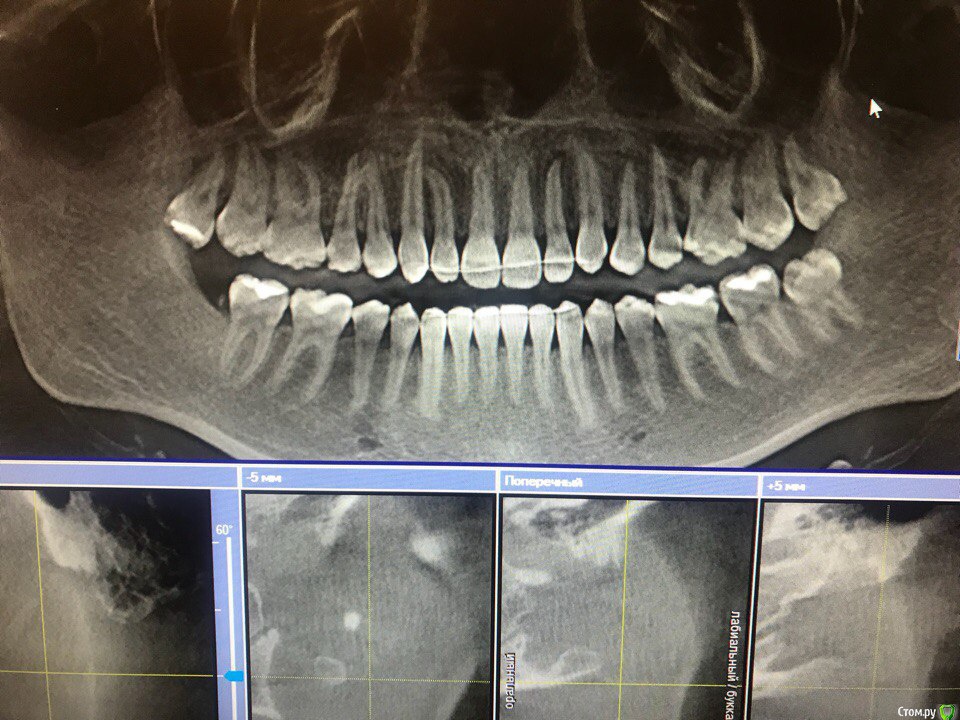

figboass Опубликовано 29 марта, 2018 Поделиться Опубликовано 29 марта, 2018 После лечения брекетами прошло 6.5 лет , столько же носятся ретейнеры. Несколько месяцев назад появилось ощущение , что имеется подвижность зубов , ретейнер на месте . Помогите определить по снимку имеется ли деструкция костной ткани? 3D снимок не загружается( Ссылка на комментарий

Kazankov.Egor Опубликовано 30 марта, 2018 Поделиться Опубликовано 30 марта, 2018 По этому криминала не видно. Есть сомнения по 22 зубу(второй левый верхний) в плане его жизнеспособности. 1 Ссылка на комментарий

figboass Опубликовано 31 марта, 2018 Автор Поделиться Опубликовано 31 марта, 2018 По этому криминала не видно. Есть сомнения по 22 зубу(второй левый верхний) в плане его жизнеспособности.А почему 22 никак себя не проявляет ?? Просто взял и стал не жизнеспособным? Ни кариеса , ни трещин , так бывает Ссылка на комментарий